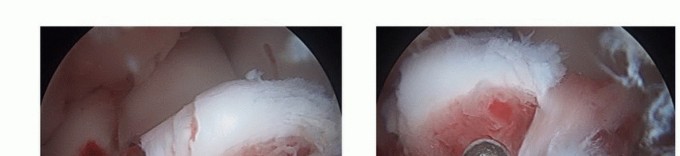

Two 1-0 polydioxanone (PDS) sutures are passed through the base of the ACL proximal to its insertion on the tibial spine (TECH FIG 3). This is most easily achieved through the midparapatellar portal.

The tibial spine is reduced in its own bed and the suture ends are tied over a bone bridge in the anteromedial portion of the tibia.

TECH FIG 3 • Arthroscopic suture fixation. A,B. Two 1-0 PDS sutures are passed through the base of the ACL. A suture passer is used to grab the suture ends through a transphyseal tunnel and the suture ends are tied in the anteromedial border of the tibia. C. Final suture fixation of a tibial spine fracture.*

The limbs of suture are luggage tagged around the base of the ACL (TECH FIG 4A), and then passed through the suture anchors.

The tibial spine fracture is reduced and the anchors are then secured anterior to the tibial eminence, angled slightly anterior to posterior (TECH FIG 4B,C).

TECH FIG 4 • Arthroscopic suture anchor fixation. A. Two limbs of 1-0 PDS suture are passed through the base of the ACL at its insertion onto the tibial eminence and luggage tag the sutures. B. The limbs of suture are passed through suture anchors and secured anterior to the tibial eminence, angled slightly anterior to posterior. C. Final suture anchor fixation of a tibial spine fracture.